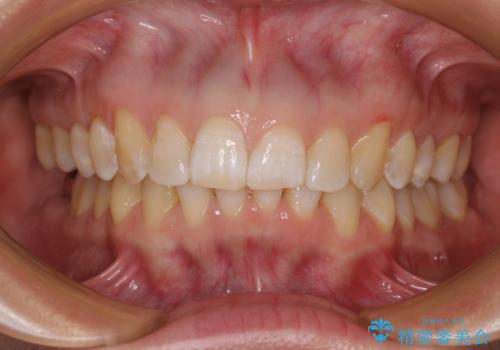

カリエールディスタライザーや部分的なワイヤー矯正を併用したことで、確実かつ短期間で治療を終えることができました。

カリエール・ディスタライザーとインビザラインを用いた前歯の咬み合わせ改善